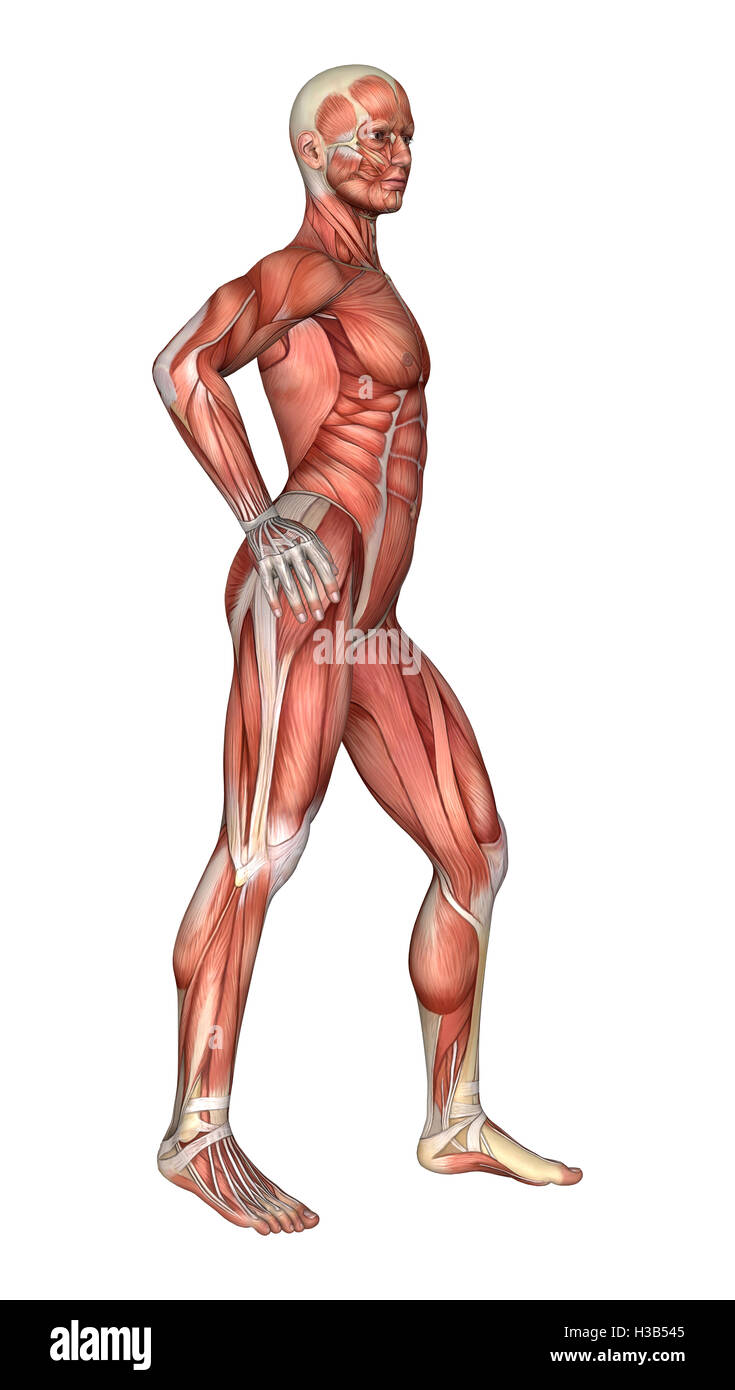

RFWW2BXR–Die männliche Anatomie, 3/4 Abbildung Muskel- und Skeletterkrankungen Systeme, Vorderansicht auf weißem Hintergrund. 3D-Anatomie Illustration.